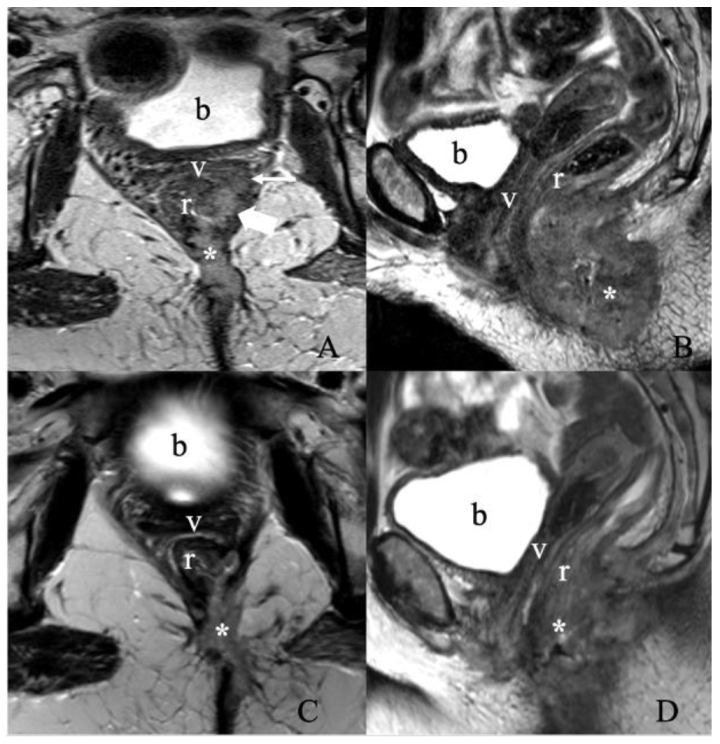

5.3. Stage III

5.4. Stage IV

| Extension to adjacent organs/structures: urethra and/or vagina with caudo-cranial extension specification; lower one-third or upper two-third; urethral meatus; bladder; fourchette area, anus/rectum |

| Lymph node involvement: inguinofemoral and/or pelvic and/or abdominal |

| Additional findings: uterus; adnexa; kidneys; and pelvic bones |